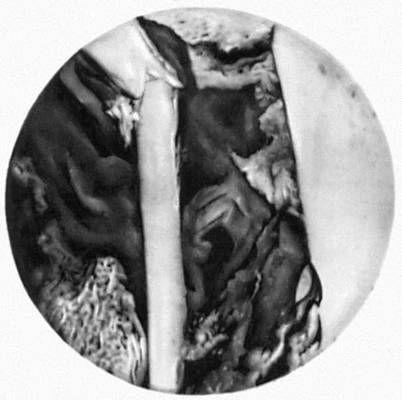

Рис. 4. Рентгеновская микрофотография среза берцовой кости человека в месте перелома (по прошествии 28 дней после перелома). Видно клеточное строение костной ткани — остеоны и остеоциты (белые точки). Увеличено.